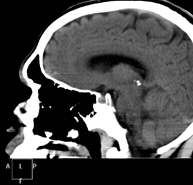

Pituitary CT

Radiological test that provides high definition anatomical images of the cerebral pituitary gland using CT (Computed Tomography) equipment. Indicated for: suspected pituitary tumour, growth disorder.